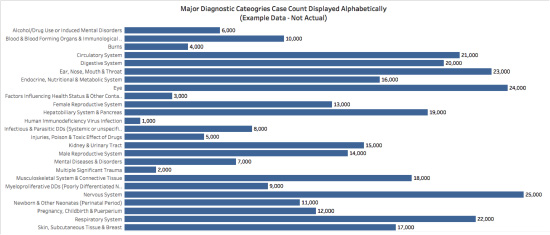

Enter the far less showy and oh-so-sensible, ever-practical bar chart. Displaying data using a bar chart affords us the ability to show the entire label for each value. Additionally, with the use of only one color, the viewer is no longer distracted by trying to understand what the different colors mean (nothing), and instead can see the shape of the data. It is also possible to directly label the value of each bar being displayed, and to rank the results or display them in some other potentially meaningful way, such as alphabetically by category.